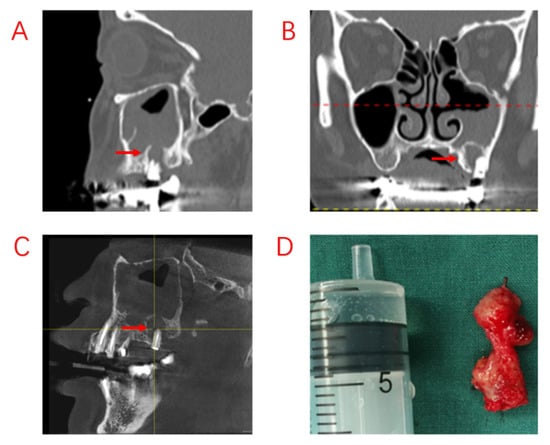

In this study, we compared the EPL, AP, and PE groups in terms of demographic characteristics, sinus symptoms, and extent of sinus invasion. The three groups were found to have statistically significant differences in terms of sex and age, with patients in the PE group being older. There were no statistically significant differences in sinusitis symptoms among ODS patients with different odontogenic etiologies. However, the proper treatment of odontogenic lesions can affect the overall outcome for the patient, and different treatments are required for different odontogenic causes. In a recently published consensus, experts in the survey agreed that a multidisciplinary approach was optimal []. We also believe that multidisciplinary collaboration is essential and have proposed different treatment approaches for different etiologies. Patients with ODS caused by AP tended to have a better prognosis, excluding those who had already had root canal treatment (RCT), root fractures, and periodontal lesions. For those patients whose lesions were limited to the apices of the teeth, infection from the pulp could be blocked by RCT, potentially avoiding the ESS procedure. Therefore, it is recommended that patients with ODS caused by periapical lesions undergo dental treatment first. The infection from the pulp was controlled with RCT, and the patients’ sinus symptoms subsequently improved as early as during the RCT procedure (Figure 2). After RCT, the decision to perform ESS was based on sinusitis symptoms and radiological findings. If the lesions are more extensive, involving root bifurcation, root fracture, or periodontal inflammation, extraction of the diseased tooth should be considered to completely remove the lesion (Figure 3). In some of our cases, the diseased teeth were extracted before the ESS procedure, but the sinusitis symptoms did not improve even after the mucosa in the oral cavity had healed. Although the pathological irritation from the oral cavity was resolved, the obstruction of the sinus openings resulted in the formation of an anaerobic environment in the maxillary sinuses, requiring the ESS procedure to improve sinus ventilation and drainage (Figure 4).

Figure 3.

Recurrence of postoperative sinus symptoms after ESS for odontogenic sinusitis due to failure to treat the apical lesion. (A,B): Large shading of the apical area of the diseased tooth and bone penetration of the maxillary sinus floor. The maxillary sinus opening was fully opened after ESS, and the maxillary sinus mucosa could not heal completely due to the apical lesion not having been removed. (C): The apical lesion persisted despite RCT of the diseased tooth. (D): A large amount of diseased granulation tissue adhered to the apical lesion. Red arrows indicate sites of apical inflammation.